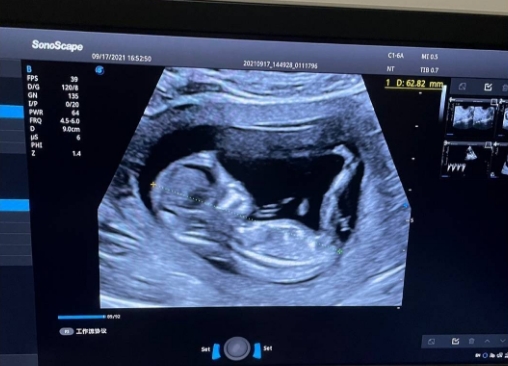

B超单子通常包括图像和文字说明。图像部分,医生会拍摄胎儿的多个角度,比如头部、四肢和生殖器官。如果你想猜测性别,重点得看生殖器官区域。但说实话,B超图并不是专门为性别鉴定设计的,它更像一张黑白“照片”,需要专业解读。我记得第一次拿到B超单时,兴奋地看了半天,结果啥也没看懂,最后还是医生一句话点醒了我。

男孩和女孩的B超特征

一般来说,在孕中期(大约20周左右),胎儿生殖器官会逐渐清晰。男孩的B超图可能显示一个小突起,俗称“小鸡鸡”,而女孩则可能看到三条线,代表阴唇。但这并不是绝对的!B超图像受很多因素影响,比如胎儿位置、羊水量等。我有位朋友,医生说她怀的是女孩,结果生下来是个男孩,闹了个大笑话。所以,别太当真,就当是个有趣的猜测吧。